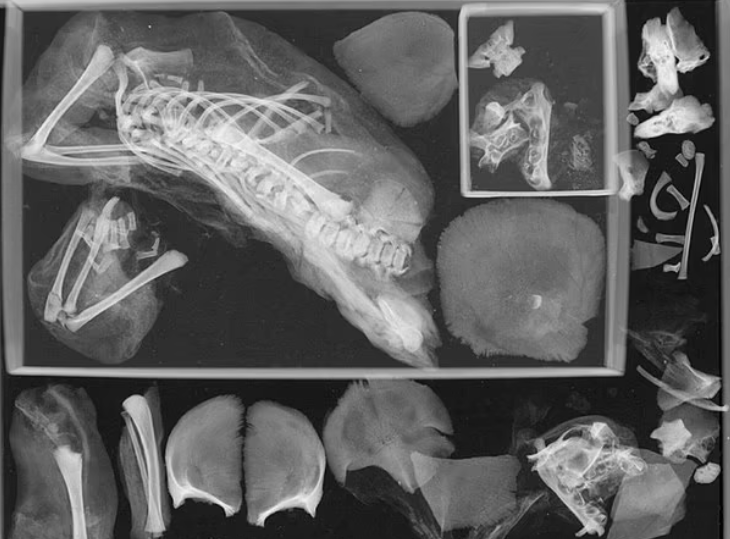

وبحسب الصحيفة، أجرى فريق من جامعة جورج واشنطن فحوصات التصوير المقطعي على الجسم، وكشف عن رأس طفل عالق في حوض السيدة وجنين آخر عالق في تجويف الصدر، وتم دفن المرأة، التي لم يتجاوز عمرها 17 عامًا، مع الطفل مقطوع الرأس، مما دفع الخبراء إلى الاعتقاد بأنها حامل بتوأم دون علمها.

ويعتقد الفريق بأن التوأم الاكبر سنا كان مقعرا ومات بسبب قطع رأس الجنين، في حين انفصل التوأم الأصغر عن الرحم وهاجر إلى منطقة ضلعها، ويُعتقد أن عمر المرأة كان يتراوح بين 14 و17 عامًا عند الوفاة، ودُفنت وذراعاها على جانبيها وقدميها مقيدين ببعضهما بواسطة الخرق، كما وضعت في طبقات من كمية كبيرة من الملح، والتي لها خصائص تجفيف تؤدي إلى تجفيف الجسم بالكامل.

تشير الملاحظات إلى أن هناك طفل مقطوع الرأس بين ساقيها ومغطى بطبقات من الملح، وحددت الأشعة المقطعية الطفل داخل التجويف العلوي الأيسر لصدر المومياء، وأظهرت عظامًا طويلة وأضلاعًا وأقواسًا عصبية وجمجمة وخمس عظام لليد.

وكتب الفريق في الدراسة التي نشرت في المجلة الدولية لعلم آثار العظام: لم يتم اكتشاف هذا الجنين من قبل، وتمكن الفريق من تحديد عمر الوفاة لدى الأطفال بما يتراوح بين 36 و40 أسبوعًا قبل الولادة، مما يثبت أنهم توأمان.